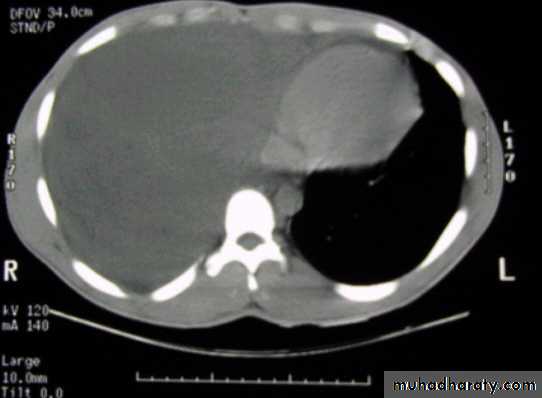

Left side massive pleural effusion with mediastinal

shift2-Ultrasonography is more accurate than plain chest radiography at determining the volume of pleural fluid. facilitates safe needle aspiration and guides pleural biopsy. may also distinguish pleural fluid from pleural thickening.

CT scan of chest showing that essentially the entire right lung volume is occupied by low attenuation fluid.